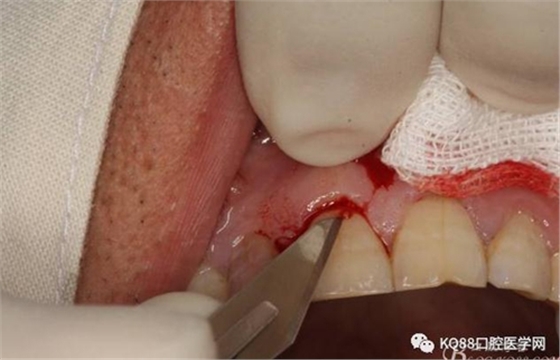

圖6.行唇側(cè)角形切口(11近中垂直切口+齦溝內(nèi)水平切口)垂直切口距離前庭溝約1~2mm。這樣可以減輕術(shù)后腫脹。

圖7. 角形切口中的齦溝內(nèi)切口情況:11號(hào)刀片伸進(jìn)齦溝內(nèi)斜切。